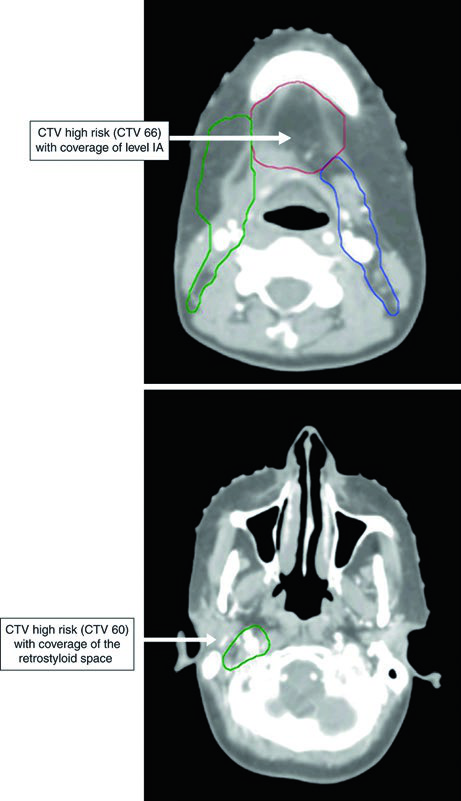

Volúmenes Blanco en Tratamiento Postoperatorio

En el escenario postoperatorio, la jerarquía cambia. El CTV66 cubre regiones de márgenes microscópicamente positivos o extensión extracapsular — situaciones que comprobadamente elevan el riesgo de recidiva local. El CTV60 engloba la enfermedad macroscópica preoperatoria, todo el lecho operatorio y el subsitio anatómico relevante, junto con los niveles ganglionares de alto riesgo. El CTV54 sigue la misma lógica del escenario definitivo: niveles de bajo riesgo subclínico.

Si existe enfermedad residual macroscópica, el GTV debe delinearse separadamente. Las dosis postoperatorias son: PTV66 = 66 Gy en 2,2–2,0 Gy/fracción; PTV60 = 60 Gy en 2 Gy/fracción; PTV54 = 54 Gy en 1,8 Gy/fracción.

La Figura 6.4 muestra un CEC de encía, T4aN1, con invasión ósea, post-resección con mandibulectomía marginal y vaciamiento cervical izquierdo. El CTV66 (rojo) cubre la región de invasión ósea. El CTV60 (verde) incluye todo el lecho operatorio y los niveles I a IV ipsilaterales.

El CTV54 (azul) abarca los niveles I a IV contralaterales. La decisión de incluir el cuello contralateral se basó en la enfermedad ganglionar positiva (N1) y el estadio T4 — ambos factores que elevan el riesgo de compromiso contralateral. En tumores de encía bien lateralizados con estadificación más favorable, esta cobertura podría omitirse.

La Figura 6.6 demuestra un CEC de piso de boca, T4aN2b, con invasión mandibular, post-hemimandibulectomía derecha y vaciamiento cervical bilateral. El CTV66 (rojo) abarca el área de extensa invasión ósea. El CTV60 (verde) incluye todo el lecho operatorio y los niveles I a V en el lado ipsilateral.

El espacio retroestiloideo ipsilateral se incluye en el CTV60 como área de alto riesgo para metástasis ganglionar, especialmente con compromiso del nivel II. El CTV60 también se extiende para incluir todo el complejo del piso de boca. El CTV54 (azul) incluye los niveles I a IV contralaterales.